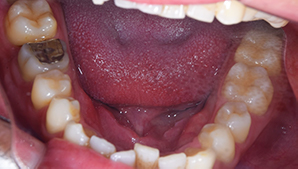

症例3

治療前

治療後

治療内容

ホワイトニングを行い、歯が白くなり、被せ物の色が周りと合わなくなったので、前歯3本の被せ物を変更しました。

治療期間 1ヶ月

治療費 合計:495,000円

(内訳)

ジルコニアボンド:165,000円×3本

治療のリスク・副作用 被せ物を外すと、ご自身の歯が少ない場合は別途はを残すための処置が必要になることがあります。